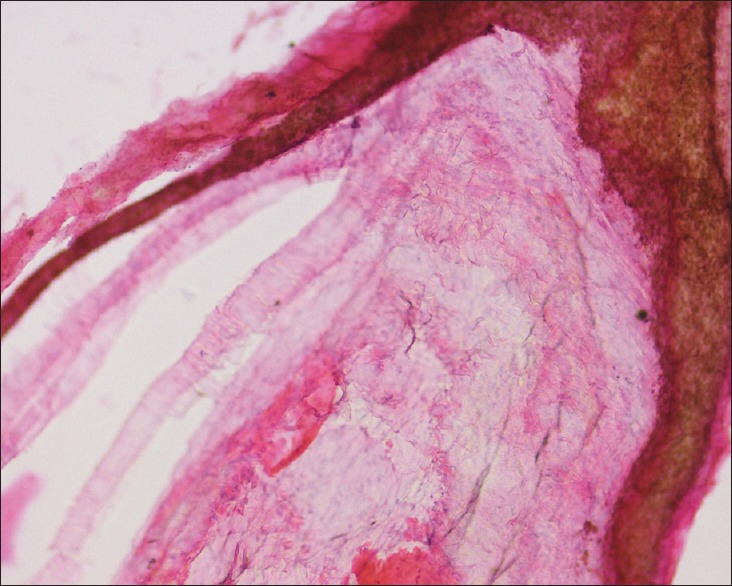

以腹股沟区肿块为表现的患者多怀疑为疝。表皮样囊肿常见于头颈部,很少由腹股沟管结构发展而来。我们在此报告一例罕见的表皮样囊肿,大小为7×8 cm,经超声诊断为腹股沟管的内容物。手术切除,病理证实为表皮样囊肿。我们的结论是,腹股沟区域的皮肤囊肿可能是一个表现,应该记住鉴别诊断。

The patients presenting with lump in inguinal area are mostly suspected as hernias. Epidermoid cyst commonly presenting in head and neck region rarely may develop from inguinal canal structures. We present here a rare case of epidermoid cyst measuring 7×8 cm as a content of inguinal canal diagnosed by ultrasonography. Surgical excision was done and confirmed as epidermoid cyst by histopathology. We conclude that cutaneous cysts in inguinal area may be a presentation and should be kept in mind for differential diagnosis.